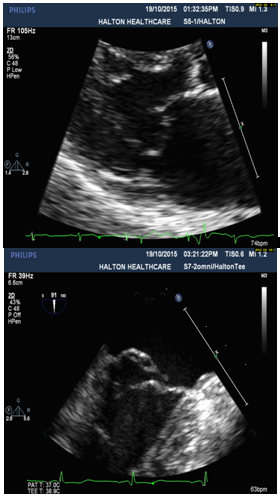

4. Thickened MV leaflets with partial flail of P2 segment of posterior leaflet, and torn chordae (Figure 1).

Figure 1: Severe MVP with Partial Flail Posterior Leaflet presented by parasternal LAX view with TTE (Left) and sagittal view at 91○ with TEE (P2 segment) (Right).

Diagnosis of MVP with flail posterior leaflet and grading of MR severity

Physical examination and 2-dimensional (2D) echocardiography are the diagnostic gold standards for MVP [4]. According to echo findings I listed above, together with the patient’s symptoms (SOB and chest discomfort) and pansystolic murmur heard at the apex, the patient was diagnosed as severe MVP with flail posterior leaflet. Echo criteria of flail leaflet includes leaflet tip pointing to LA without systolic coaptation (Figure 1,2,4), torn chordae, double contour (parallel sign) between flail and normal leaflets (Figure 4), and eccentric MR jet direction opposite to the location of the flail leaflet (Figure 2 and 4) [3,4]. Doppler echocardiography is essential in determining the severity of MR. According to ASE guideline, criteria for severe MR includes a vena contracta width ≥ 0.7 cm, large central mitral regurgitation jet (area >40% of left atrium), pulmonary vein reversal, effective regurgitant orifice >40 mm2 and others [3,5]. The echo findings and Doppler measurements strongly support a severe MR in the patient (Table 1).

When MVP with flail leaflet was diagnosed by TTE, next step should consider which scallop segment can be involved in the defect. TEE is effective in identifying prolapsing segments with multiple plans. Anatomically, the posterior and anterior leaflets of the mitral valve each may be divided into three sections. Carpentier’s widely recognized nomenclature describes three posterior leaflet scallops–the lateral (P1), middle (P2), and medial (P3)-and three anterior segments (A1), (A2) and (A3) [2,3]. According to clinical studies, P2 is the most common site of localized prolapse and flail due to myxomatous degeneration and fibroelastic dysplasia [2]. In this study, localized P2 segment defect was identified by sagittal view (long axis) of TEE.